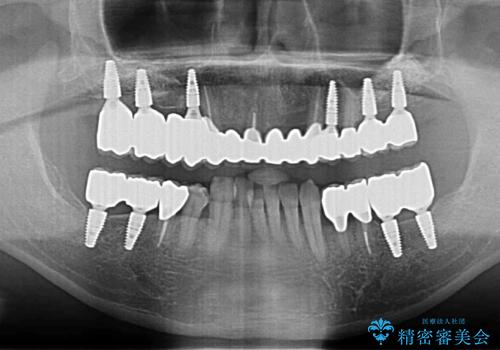

クラウンを装着した歯の虫歯の再発を防ぎ長い予後を期待するために削った箇所をしっかりとかぶせる適合の良さが必要はもちろんですが、セメントの漏洩を防ぐためにクラウンの十分な支台高径を歯周外科を行い獲得しました。